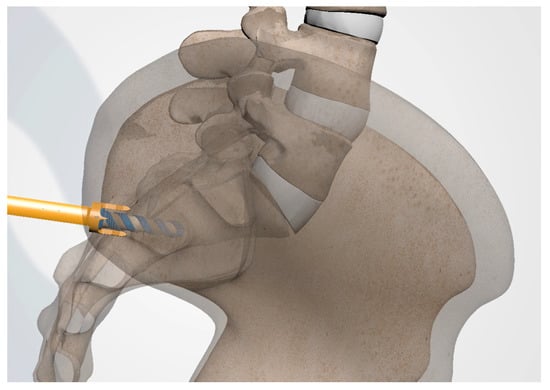

3.3.5. Tissue Dilation

3.3.6. Implant Preparation